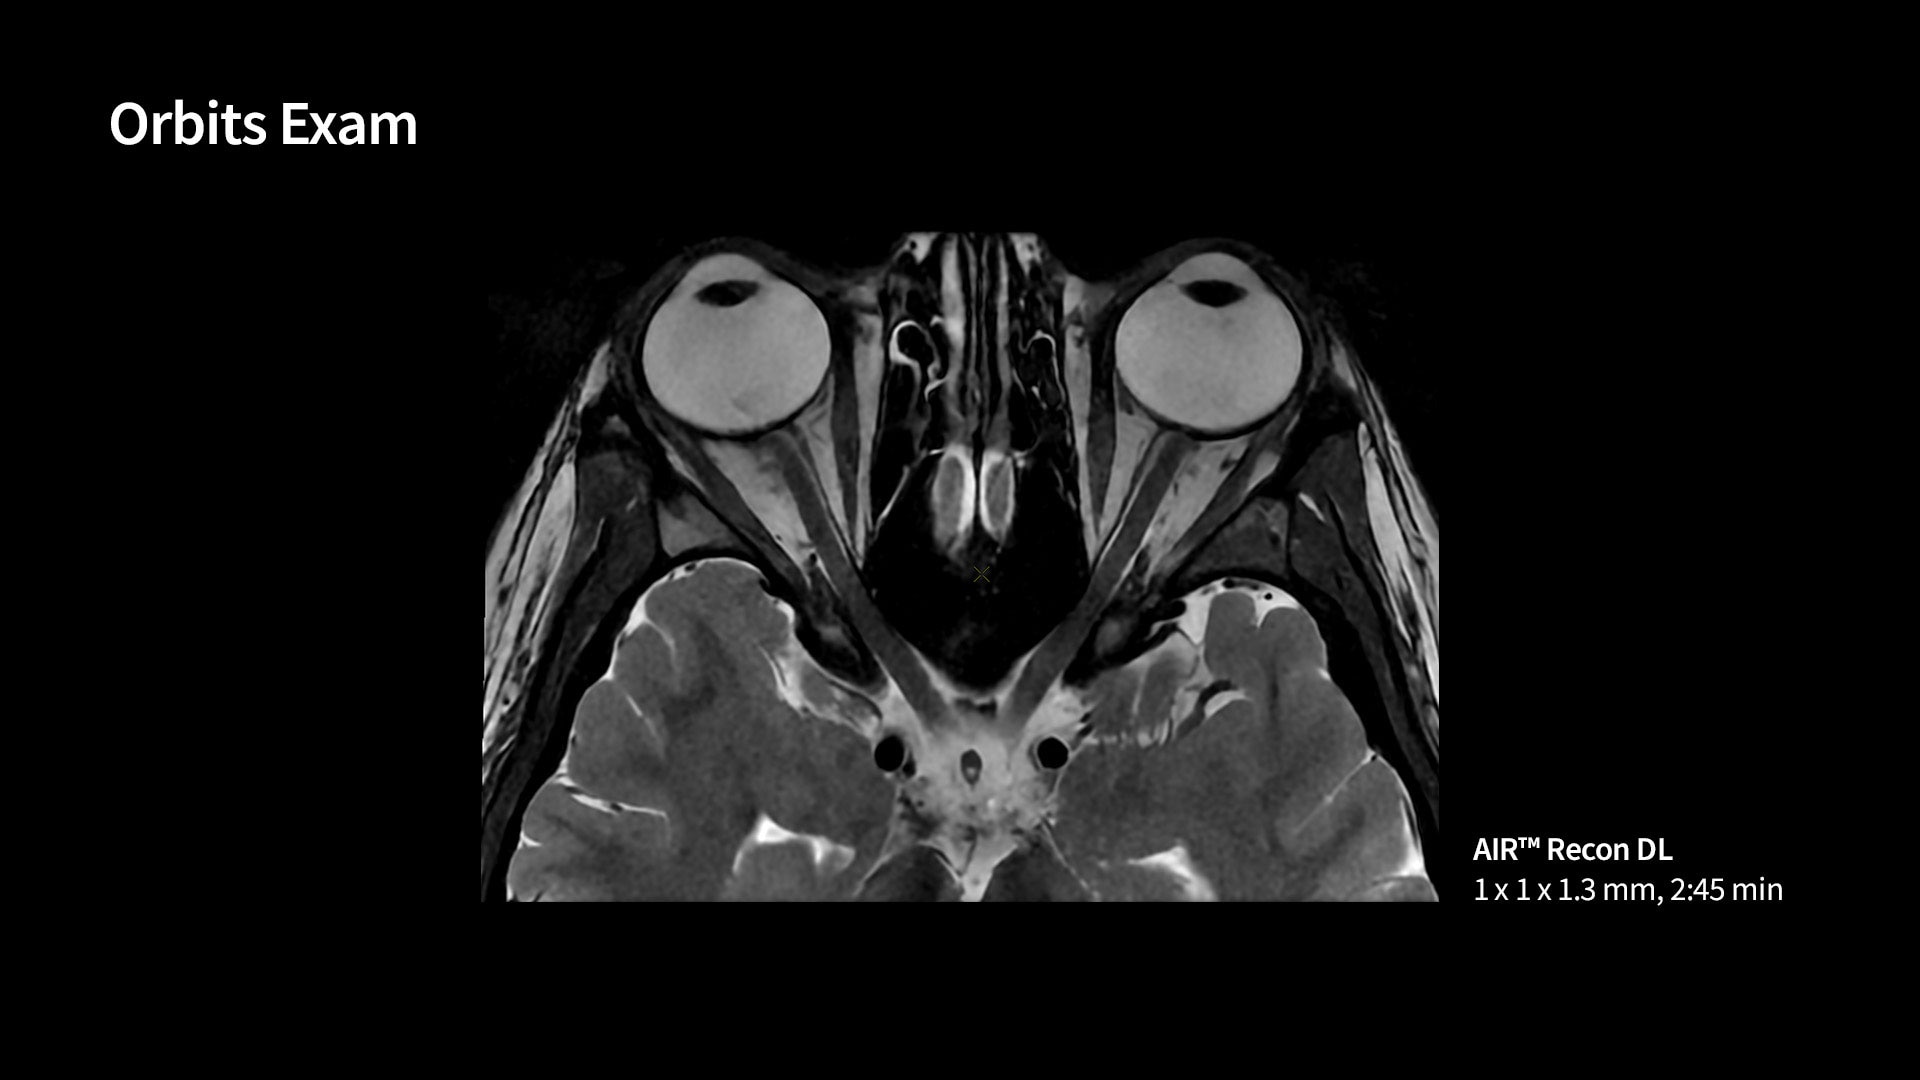

MR image reconstruction with AIR™ Recon DL

AIR™ Recon DL has revolutionized MR imaging with deep-learning based image reconstruction increased image quality, reduced scan time and improved SNR.